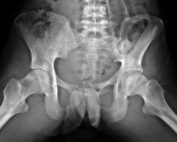

The hip joint in the pelvis is a ball-and-socket joint formed by the head of the femur at the top of the thigh fitting into the acetabulum, a socket covered in a slippery tissue called articular cartilage. (See hip anatomy image.) This cartilage helps protect the joint and allows the joint to move smoothly with very little friction. In patients who have hip impingement, this cartilage is worn away quicker than in normal hips because misaligned, abnormally-shaped bones move rigidly against each other causing a breakdown of cartilage. Femoroacetabular impingement (FAI) is caused when bony overgrowths in the hip joint rub against the acetabulum preventing smooth motion of the joint.

Dr. Nwachukwu will examine the hip to determine if femoroacetabular impingement is the cause of a patient’s symptoms. He will conduct a detailed physical exam, consisting of multiple tests. One specific maneuver is called an impingement test, where he moves the knee closer to the chest and then rotates it in towards the shoulder. If this causes groin pain, FAI may be the diagnosis. In almost all cases, Dr. Nwachukwu will also use imaging to evaluate the joint. X-rays provide the opportunity to look at the bone itself and determine if they are misshapen. In many cases, Dr. Nwachukwu will also utilize an MRI (magnetic resonance imaging) scan to examine the soft tissues and cartilage within the hip to evaluate the hip labrum, cartilage and other soft tissue structures around the hip.